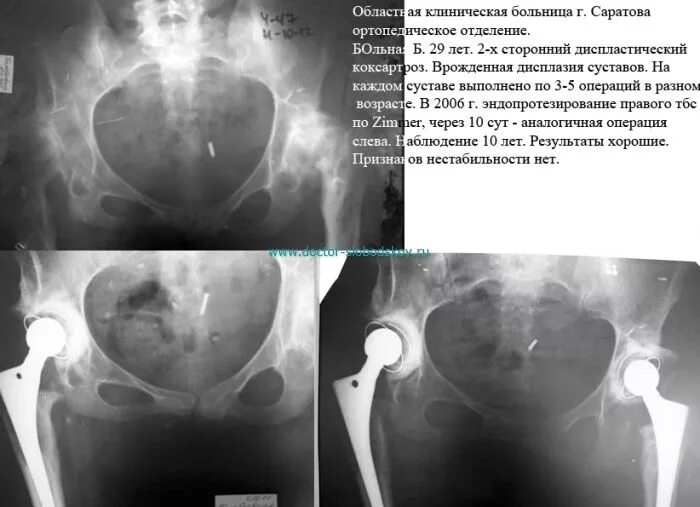

Коксартроз тазобедренного 3 степени операция